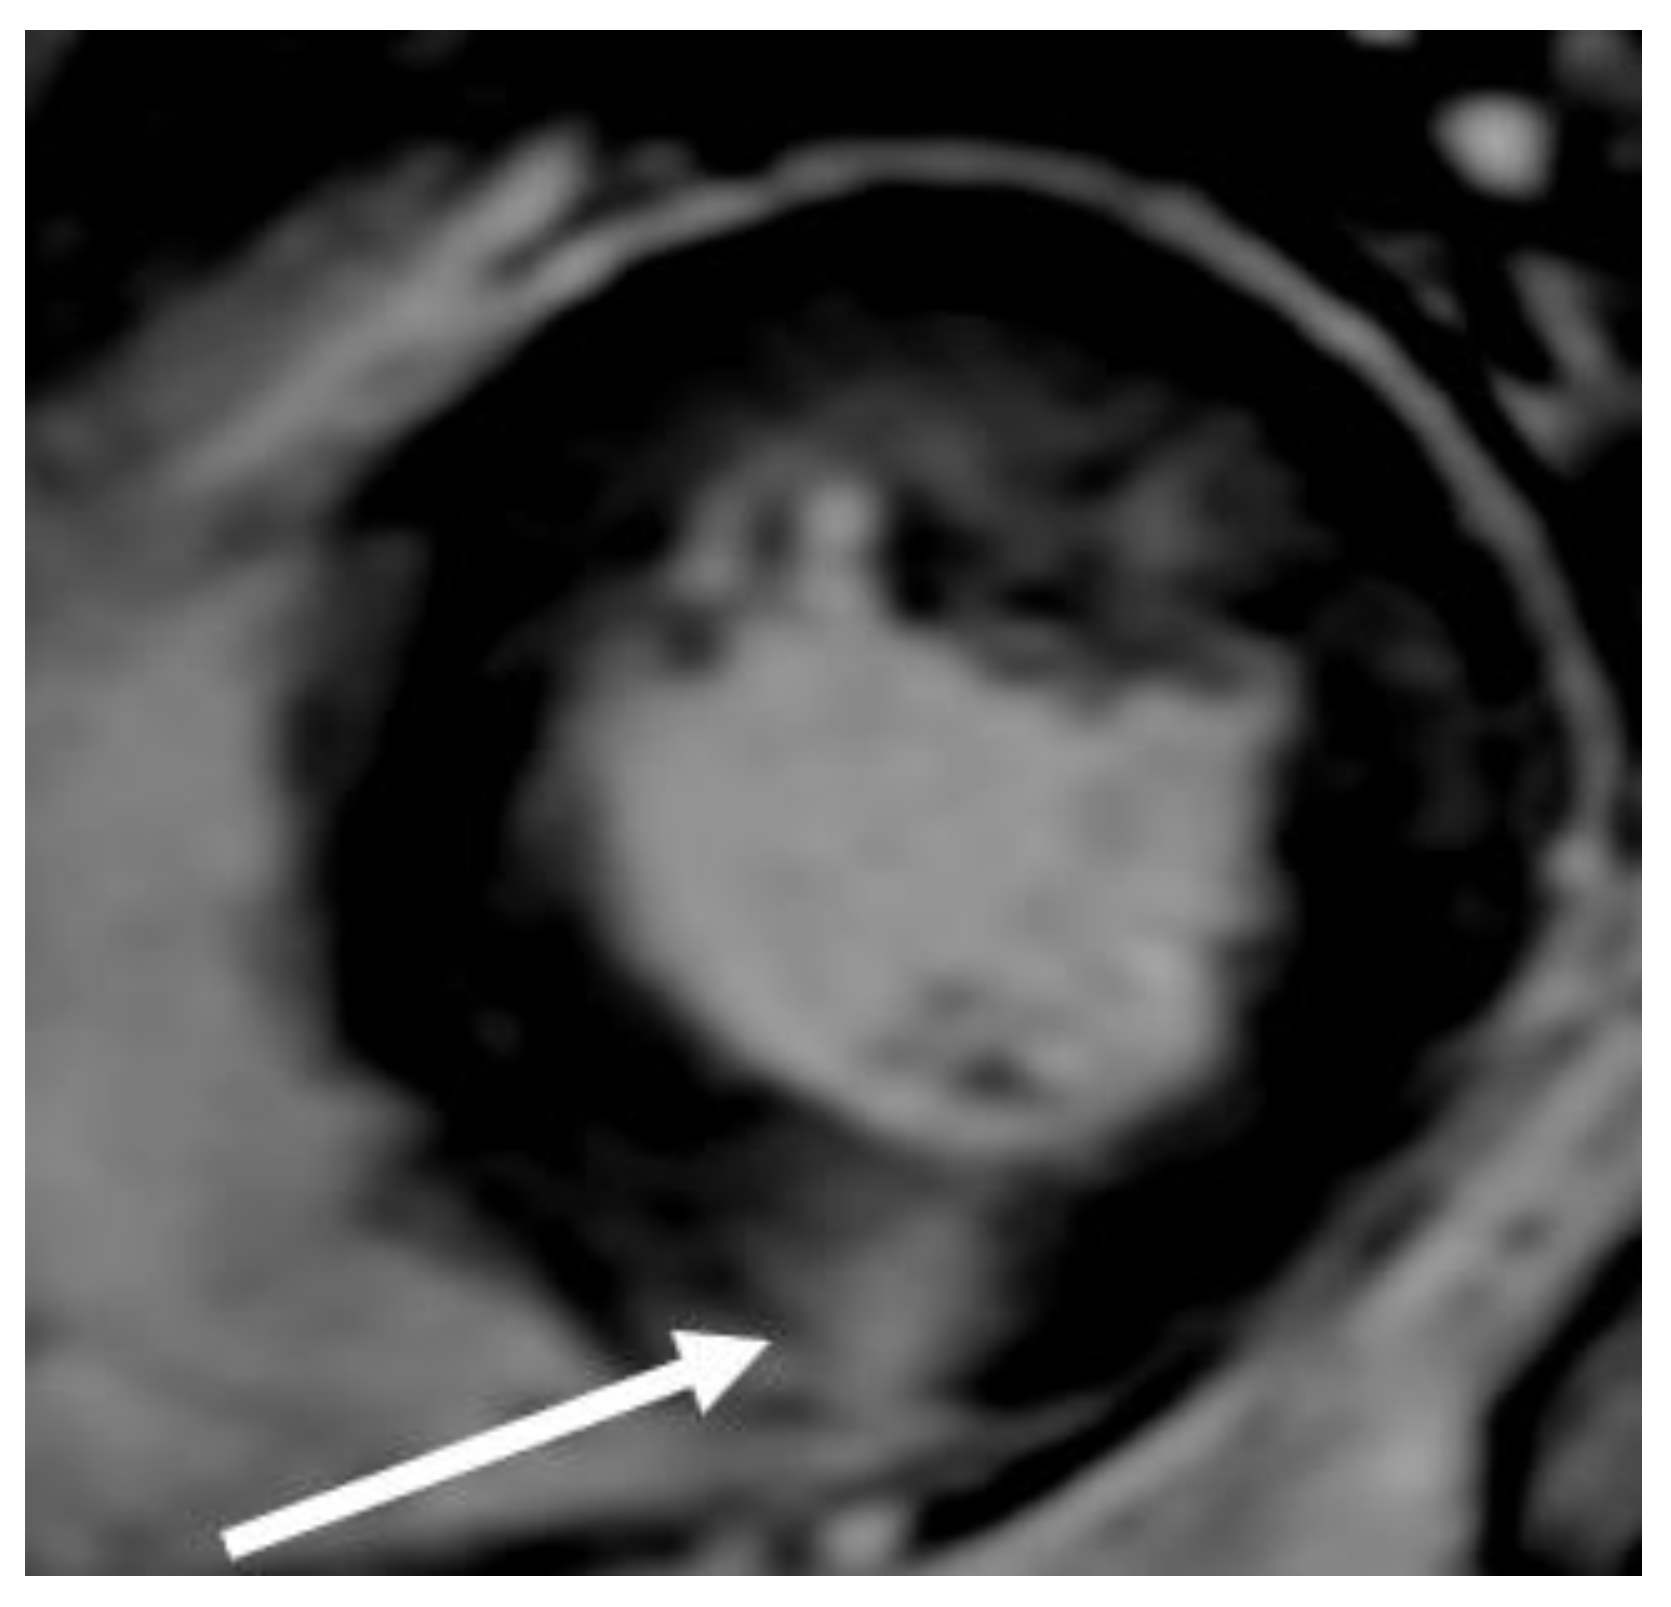

Figure 5. Mid-cavity obstruction; typical hourglass appearance of left ventricle (arrow).

When evaluating the presence and severity of obstruction in HCM, a systematic assessment of all the components of the mitral valve apparatus via 2D echocardiography is required. This technique allows a visualization of the presence and distribution of LV hypertrophy, the presence of SAM, elongation of mitral valve leaflets, displacement of papillary muscles, laxity of tendon cords and LVOT diameter reduction (Figure 2). In addition, 2D echocardiography allows a diagnosis of MCO via the observation of a typical hourglass appearance of the LV due to systolic septal contact with the anterolateral wall, which induces sphincter-like cavity obliteration, creating two distinct (basal and apical) LV chambers (Figure 5). In addition, 2D echocardiography allows a visualization of the presence of an apical aneurysm and any thrombotic formation. In this setting, contrast echo may also be helpful for the correct diagnosis.